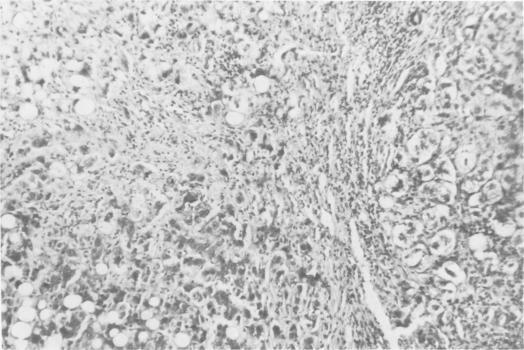

Preoperative cardiovascular hemodynamics and percutaneous liver biopsies were used to evaluate the pathophysiologic factors determining the operative prognosis of patients with cirrhotic liver disease and bleeding esophageal varices. These studies confirm the observations of Siegel that the greater the magnitude of the peripheral abnormalities in vascular tone and oxygen consumption the better must be the capability of the ventricular function, if the cirrhotic is to survive emergency or urgent portal decompressive surgery. These studies also show that the cardiovascular hemodynamics are directly correllated with the nature and degree of the abnormalities in the liver biopsy, and that pathologic and physiologic features of this disease which impact on surgical prognosis can be expressed through the easily obtained Survival Index. Bleeding cirrhotic patients with poor quality hemodynamics and poor histologic characteristics should be treated non operatively, since the operative mortality appears greater than that produced by a strategy of medical supportive therapy and delayed surgery if stabilization occurs.

Acute hyaline necrosis of the liver. A surgical trap.肝脏急性透明样坏死。一个手术陷阱。

The influence of acute hyaline necrosis on survival after emergency and elective portacaval shunt.